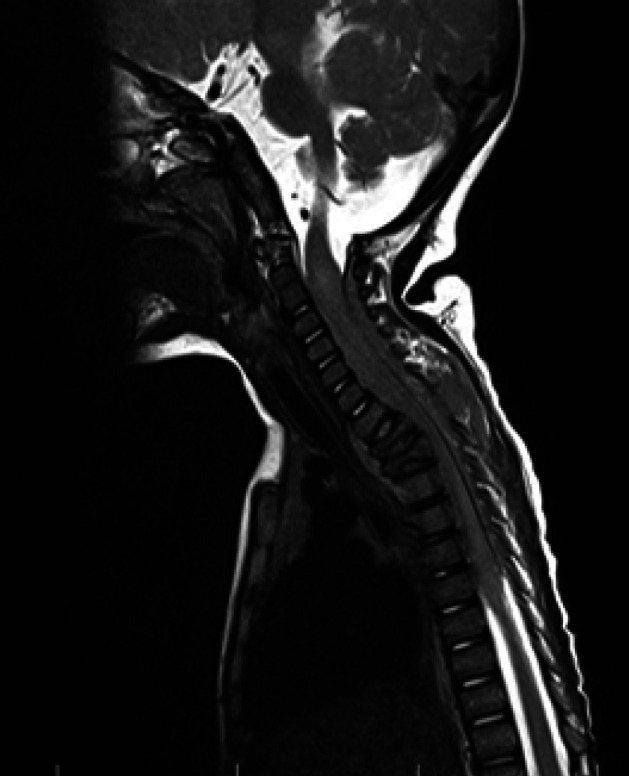

Ewing sarcoma (ES) is a highly malignant tumor originating from bones, exceptionally long bones. ES arising from the epidural extramedullary space, primarily the cervical region, is highly unlikely. There have been only six cases of cervical epidural extraskeletal Ewing sarcoma (EEES) in children reported in the literature, all of whom were older than seven years old. Four of seven cases, including the one mentioned in this study, were male (57%). Herein, we report a 1.5-year-old girl who presented with quadriparesis without cognitive impairment and had initially undergone a metabolic disorder evaluation. The spine MRI revealed a mass in the C2-T6 region, and she underwent a biopsy of the tumor via laminectomy. Microscopic examination confirms a diagnosis of ES based on immunohistochemistry. This is the first literature that presents an infant with EEES.